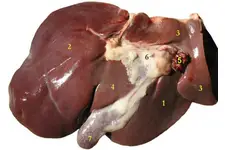

Yenidoğanda Kistik Fibrozis Belirtileri ve Tedavisi Kistik fibrozis (KF), genetik bir hastalık olup, vücuttaki mukus, ter ve sindirim sıvılarının anormal şekilde kalınlaşmasına neden olur. Bu durum, özellikle solunum ve sindirim sistemlerini etkileyerek ciddi sağlık sorunlarına yol açabilir. Yenidoğan döneminde kistik fibrozisin tanınması, erken müdahale ve tedavi açısından son derece önemlidir. Bu makalede, yenidoğanda kistik fibrozis belirtileri ve tedavi yöntemleri detaylı bir şekilde ele alınacaktır. Kistik Fibrozisin Nedenleri Kistik fibrozis, CFTR (Cystic Fibrosis Transmembrane Conductance Regulator) genindeki mutasyonlar sonucu ortaya çıkar. Bu genin normal işleyişi, vücutta mukus salınımını düzenler. Mutasyona uğramış bir CFTR geni, mukusun kalınlaşmasına ve yapışkan hale gelmesine neden olur. Bu durum, akciğerler ve sindirim sistemi gibi organlarda ciddi hasarlara yol açabilir. Yenidoğanda Kistik Fibrozis Belirtileri Yenidoğan döneminde kistik fibrozisin belirtileri genellikle doğumdan hemen sonra veya ilk birkaç ay içinde ortaya çıkar. Bu belirtiler şunlardır:

Tedavi Yöntemleri Kistik fibrozis tedavisi, hastalığın belirtilerini yönetmeyi ve yaşam kalitesini artırmayı amaçlar. Tedavi yöntemleri arasında: